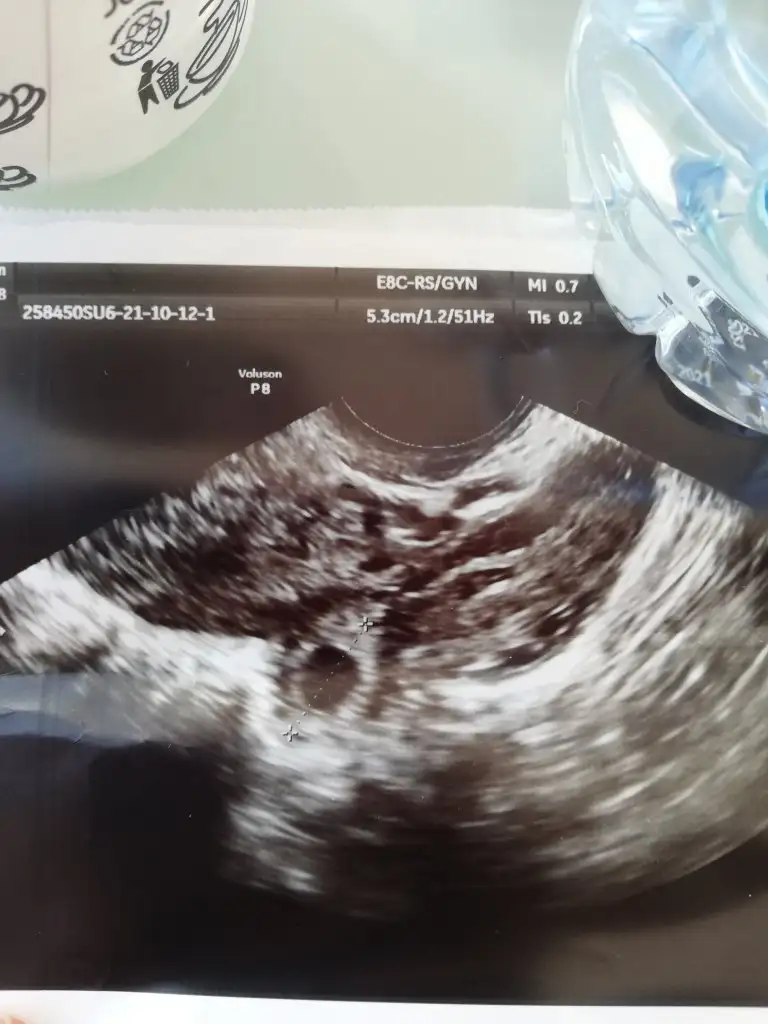

Alttan baktı göremeyince baya uzun sürdü bilmiyorum canım başka hastanaye geldik kan sonucu bekliyorum

IMG_20211012_095214.webp

Kese var yolk da var dedi

Karından ultrason da gözükmüyor kuzum alttan gözüktü alttan da ikinci doktor bakmadı tehlikeli diye gerçekten mi kızlar ben umudumu kaybettim

alttan bakıldığında gözüktü ama değil mi ? attığında görüntüde gözüküyor yani. içini ferah tut ve hemen o diğer doktoru şikayet et. sağlam gebeliği bitirmeye kalkıcaktı